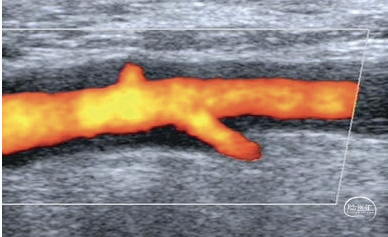

动脉超声因其成本低、普及广且无辐射暴露而常被早期使用;但其操作者间变异性较高,需要具备该领域的专业知识。推荐将双侧颞动脉和腋动脉超声作为疑似巨细胞动脉炎的首选影像学检查方法,其汇总敏感性估计为88%,特异性为96%。急性动脉炎症的典型表现为不可压缩的晕征(图2),即均匀的低回声环形管壁增厚,且探头压迫下不消失。尽管并非病征性,但颞动脉和腋动脉同时出现晕征可增强超声对巨细胞动脉炎的诊断性能。动脉超声在大动脉炎中也可能有用,特别是在检测结构性病变方面。除胸降主动脉外,大多数动脉(如颈动脉、椎动脉、锁骨下动脉、肠系膜动脉和肾动脉)都可通过超声检查,但随着动脉位置加深,分辨率会下降。

图2.超声显示的巨细胞动脉炎动脉炎症。动脉超声是一种成本低廉且广泛普及的检查技术,目前被推荐作为疑似巨细胞动脉炎的首选影像学检查方法。该技术能有效检测结构性病变和血管壁炎症性改变,例如颞动脉(A)与腋动脉(B)中显示的不可压缩性晕征。晕征表现为均匀的低回声环形管壁增厚,在探头加压时不会消失,虽非病征性表现,但具有较好的诊断准确性: